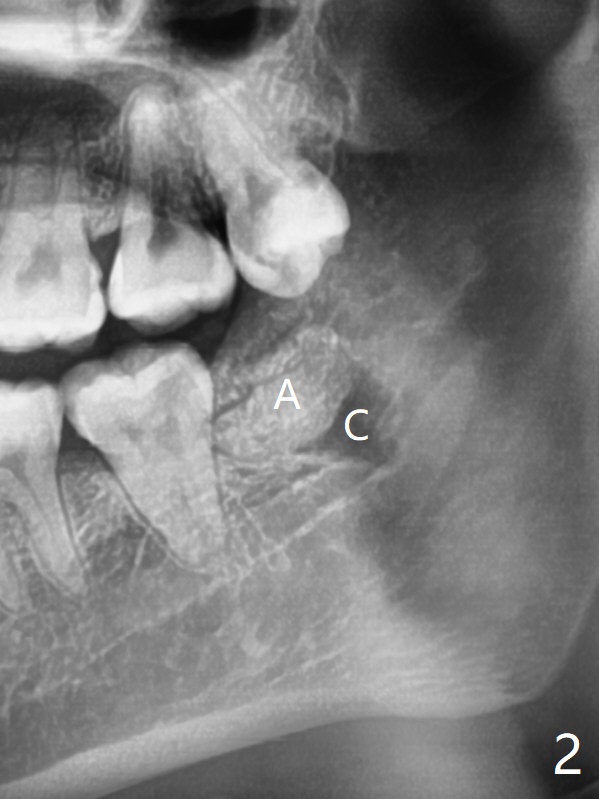

A 24-year-old woman with poor oral hygiene presents to clinic requesting extraction of the tooth #17 (Fig.1). The tooth is removed after multiple sectioning. One half of collagen plug is placed in the bottom of the socket (Fig.2 C, while 1 cc of Bond Apatite in the coronal portion of the socket (A). The other half of the collagen plug is placed on the top of the cement before suturing with 4/0 PGA. The patient feels pain when the tooth is wiggled heavily. But the Inferior Alveolar Canal is not exposed when the tooth is out. Return to Plug Cement Xin Wei, DDS, PhD, MS 1st edition 07/14/2020, last revision 07/14/2020